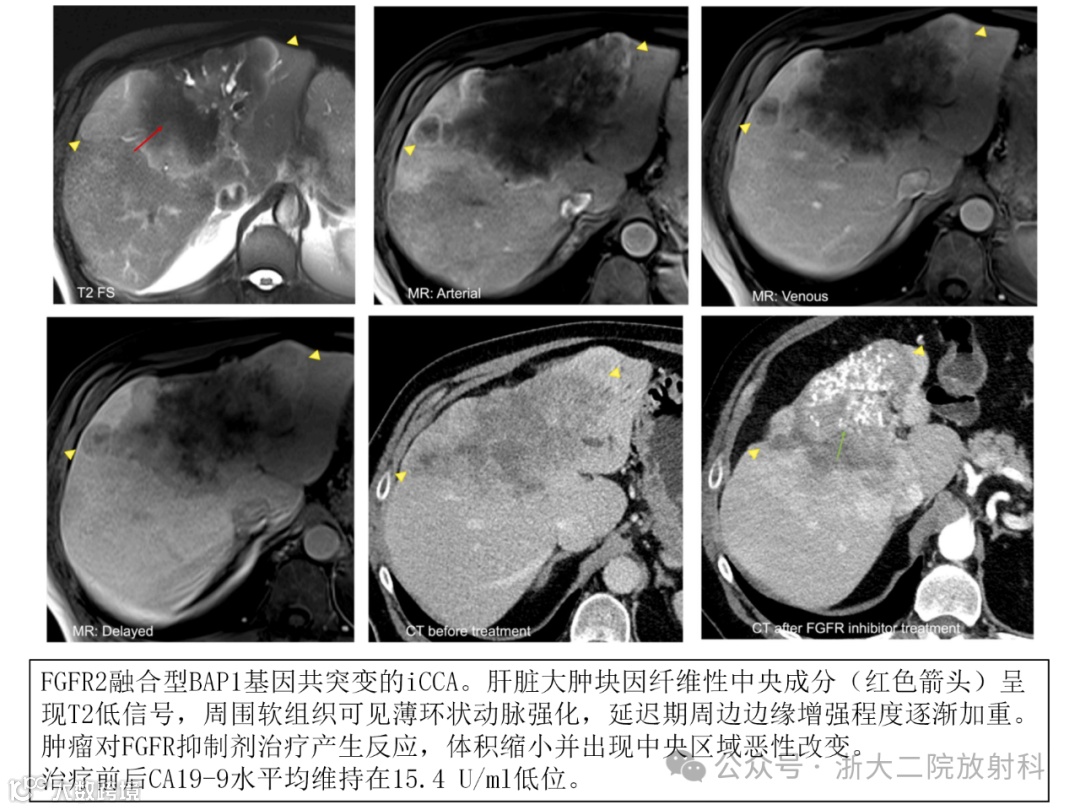

肝内胆管癌的分子特征:在靶向治疗选择中的作用